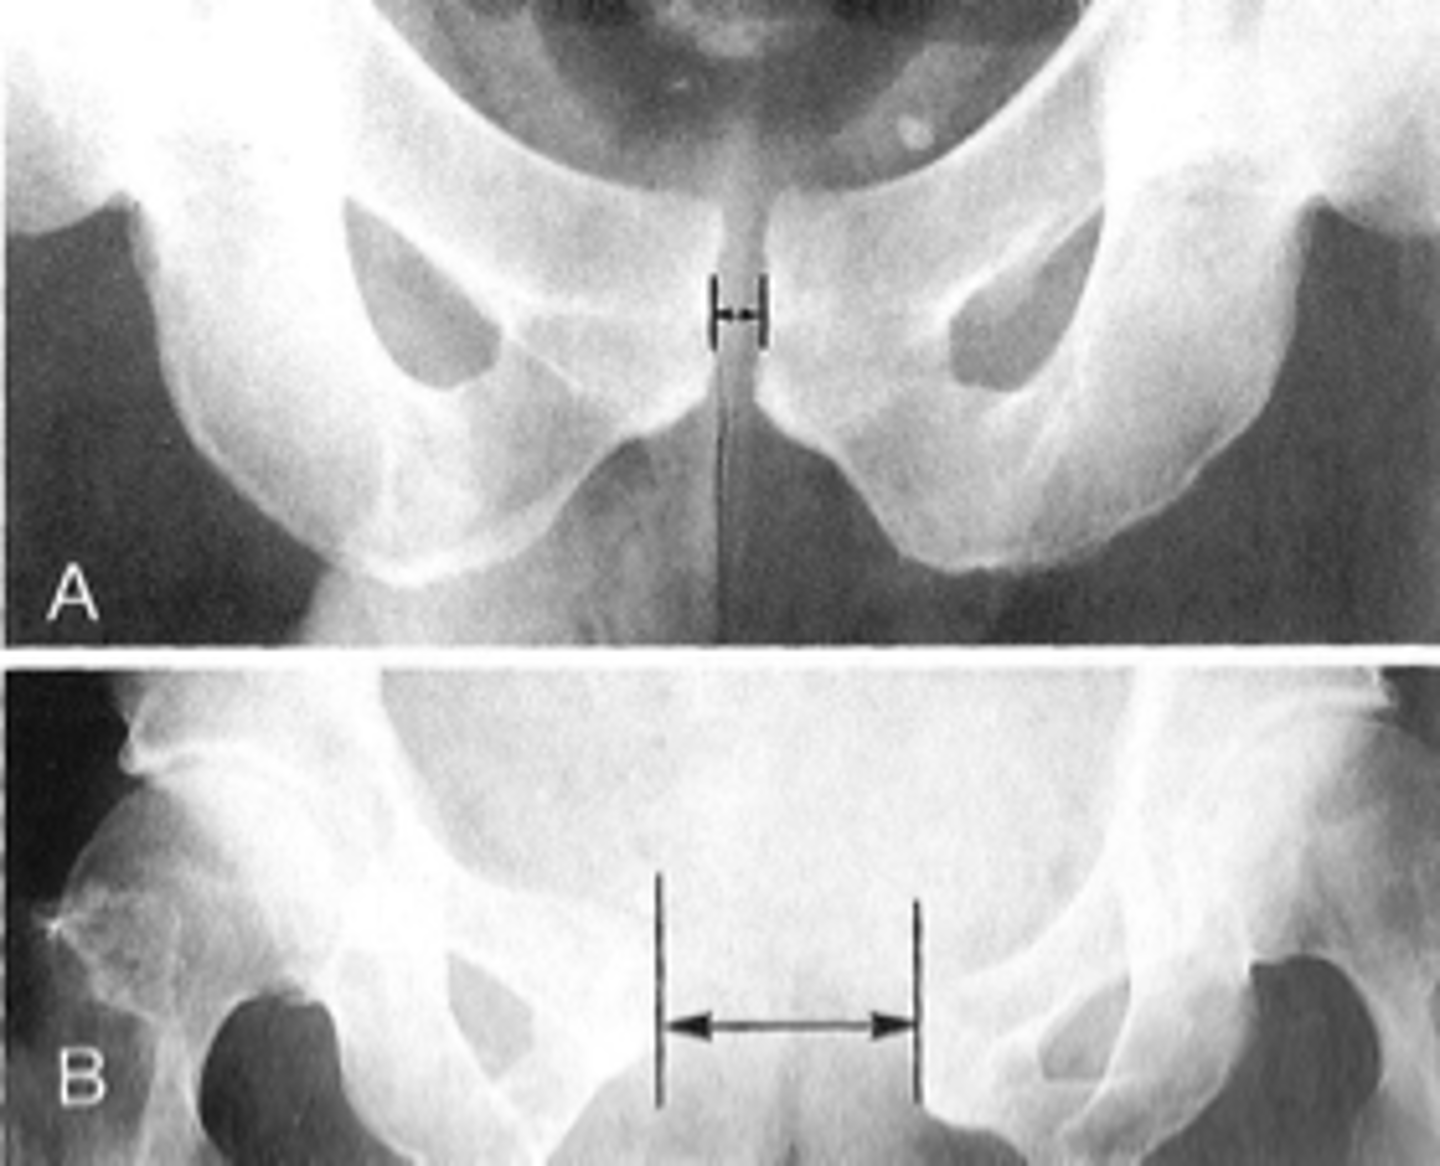

- AP pelvis

- Frog-leg pelvis

State the standard bilateral pelvis projections

AP pelvis

ID standard bilateral pelvis projection

Frog-leg pelvis

Pubic symphysis

ID 1

<p>ID 1</p>

ID 2 (joint)

<p>ID 2 (joint)</p>

ID measurement line

<p>ID measurement line</p>

- AP hip

What views are needed to see Kohler's teardrop distance?

<p>What views are needed to see Kohler's teardrop distance?</p>

- Medial margin of femoral head

- Lateral border of teardrop

Kohler's teardrop distance landmarks

<p>Kohler's teardrop distance landmarks</p>

6-11 mm

Normal Kohler's teardrop distance measurement

<p>Normal Kohler's teardrop distance measurement</p>

2 mm

The normal Kohler's teardrop distance is 6-11 mm, and there should be no greater than a _____ difference when comparing to the contralateral side

<p>The normal Kohler's teardrop distance is 6-11 mm, and there should be no greater than a _____ difference when comparing to the contralateral side</p>

Hip joint effusion

Clinical significance of an enlarged Kohler's teardrop distance

<p>Clinical significance of an enlarged Kohler's teardrop distance</p>

Waldenstrom's sign

What sign indicates an enlarged Kohler's teardrop distance?

- Accentutation of the normal limits

<p>What sign indicates an enlarged Kohler's teardrop distance?</p><p>- Accentutation of the normal limits</p>

Symphysis pubis width

ID measurement

What view is used to see the symphysis pubis width?

Distance between opposing articular surfaces

Symphysis pubis width landmarks

8 mm

Maximum symphysis pubis width measurement in adults

<p>Maximum symphysis pubis width measurement in adults</p>

10 mm

Maximum symphysis pubis width measurement in children

<p>Maximum symphysis pubis width measurement in children</p>

Pregnancy/postpartum

The symphysis pubis width may be larger in _____

Diastasis

Clinical significance of a widened symphysis pubis